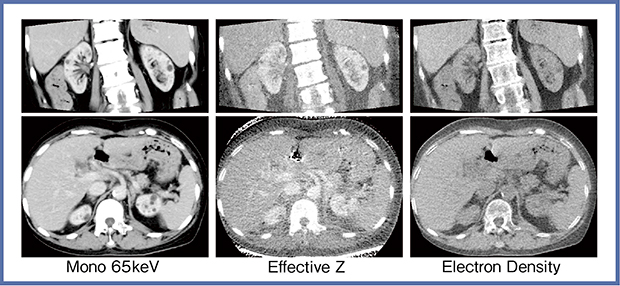

実効原子番号(Effective Z)は,あるボクセルを単一の原子で置き換えると仮定した時に,そこに該当する原子番号のことであり,どちらかというとCT値に近い振る舞いをする。一方の電子密度(Electron Density)は,単位体積内に存在するであろう電子の個数を表しており,コンプトン散乱に影響を与えることから放射線治療の領域で注目されている。電子密度は,CT値とは大きく異なる振る舞いをすることがある。図6は,仮想単色X線画像(65keV),実効原子番号と電子密度の腹部の画像である。実効原子番号画像では造影されている部分が白く,通常のCT画像に近いコントラストだが,電子密度画像では単純CTのようなコントラストとなっている。

図6 実効原子番号,電子密度の腹部画像例